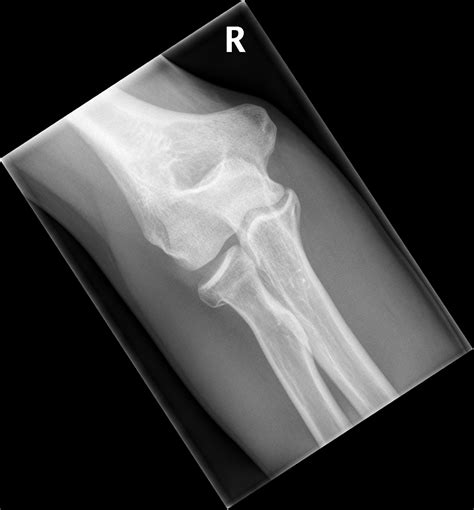

Elbow Joint Effusion occurs when there is an abnormal accumulation of fluid within the joint capsule. The elbow joint is lined with a thin membrane called the synovium, which produces a small amount of fluid to lubricate the cartilage and allow for smooth movement. When the joint is irritated—due to trauma, infection, or chronic inflammatory diseases—the synovium overproduces this fluid, leading to swelling, stiffness, and restricted range of motion.

Because the elbow joint capsule is relatively tight, even a small increase in fluid volume can cause significant pressure. This pressure is often what leads to the sharp pain or aching sensation patients report. It is important to distinguish effusion from bursitis, as the former occurs inside the joint space, whereas bursitis typically occurs in the bursa sac outside the joint.

Anatomical representation of the elbow joint

• elbow joint effusion x ray